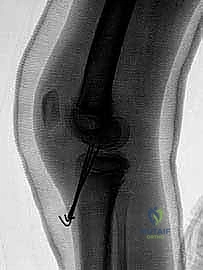

2. التصوير بالأشعة السينية (X-rays)

هي الخطوة الأولى والأساسية. يطلب الدكتور هطيف صوراً بأوضاع متعددة:

* صورة أمامية خلفية (AP): لرؤية الهيكل العام.

* صورة جانبية (Lateral): وهي الأهم لرؤية شوكة الظنبوب وتقييم درجة ارتفاعها وإزاحتها (لتحديد تصنيف مايرز ومكيفير).

* صورة النفق (Tunnel View): لرؤية الشق بين اللقمتين بوضوح.